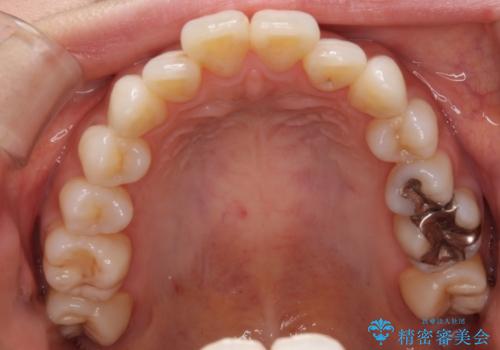

裏側のワイヤー矯正 抜歯して前歯をしっかり後ろに下げる

- 出っ歯が気になるとのことで来院されました。

上顎の、前から4番目の歯を左右1本ずつ抜歯して前歯を後方に下げる計画としました。

目立たずに矯正をご希望でしたので、裏側矯正で治療を行いました。

上下裏側矯正であったため、舌に傷や口内炎ができるなどつらい経験もされましたが、目立たずに治療できたことに喜んでいただけました。